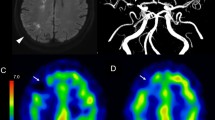

The neurological scores of the rats in the rTMS group were higher than in those of the control group over the whole 7-day observation period. The total, cortical and striatal infarct volumes were significantly less in the rTMS group than in the control group, as measured by 2,3,5-triphenyltetrazolium chloride staining. 18F-FDG microPET images showed significantly higher standardized uptake values in the cortex and striatum in the rTMS group than in the control group in the affected hemisphere. The number of cells positive for caspase-3 was significantly lower in the rTMS group than in the control group, while the Bcl-2/Bax ratio was significantly higher in the rTMS group than in the control group.

rTMS therapy increased glucose metabolism and inhibited apoptosis in the ischaemic hemisphere. 18F-FDG PET could be used to monitor rTMS therapy in transient cerebral ischaemia in animal studies and in future clinical trials.